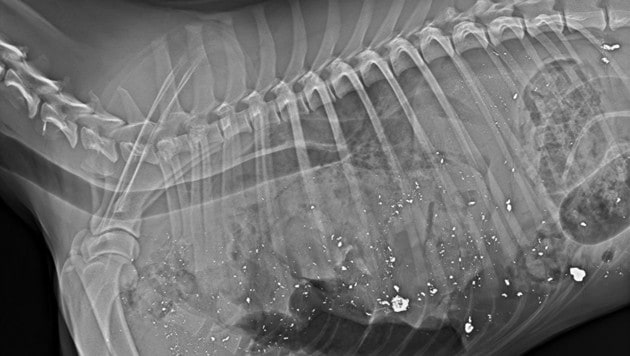

„Habe Röntgen-Beweis, dass Jäger Unwahrheit sagt“

Der Besitzer (30) des in Oberösterreich erschossenen Border Collies „Cooper“ widerspricht nun den Angaben des Todesschützen (84). Die Grünen habe zu dem Fall eine aktuelle Landtagsanfrage an die Jagdlandesrätin (VP) eingebracht.

Der vierjährige Border Collie „Cooper“ ist tot – erschossen von einem Jäger, der ihn am 27. Dezember auf einem Forstweg in Pettenbach im Traunviertel mit einem Fuchs verwechselt haben soll. Angeblich bemerkte der 84-Jährige vom Hochstand aus „ein Tier mit buschiger Lunte“, das der Fährte eines Rehs folgte.